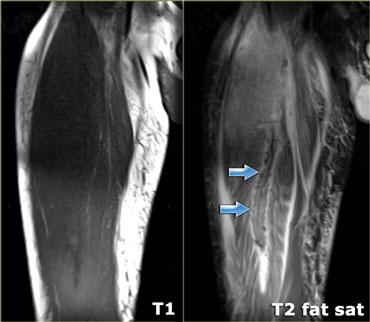

Muscle Strain

Căng cơ là chấn thương tại điểm nối cơ-gân.

Điểm nối gân là nơi các sợi cơ gặp gân, và hình dạng của nó khác nhau ở các cơ khác nhau.

Ở nhiều cơ, gân kéo dài sâu vào trong cơ tạo thành điểm nối cơ-gân dài (hình).

Vùng này đặc biệt quan trọng trong bối cảnh chấn thương, vì nó thường hay bị tổn thương.

Hình thái phù nề trong chấn thương cơ sẽ phụ thuộc vào cấu trúc và hình dạng của chỗ nối cơ-gân liên quan.

Hình ảnh bên trái cho thấy phù nề xung quanh chỗ nối cơ-gân theo dạng hình lông vũ.

Đặc điểm điển hình của căng cơ là có nhiều phù nề xung quanh chỗ nối cơ-gân vì đây là nơi xảy ra rách.

Có phù nề xung quanh gân và đôi khi bản thân gân sẽ có thay đổi tín hiệu.